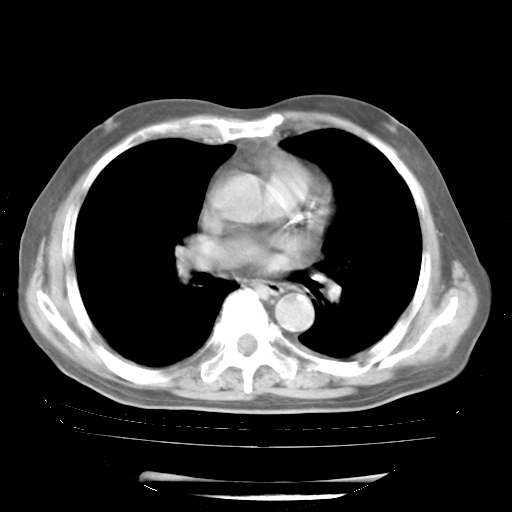

4月28日肺部CT——再次出现类似去年5月9日——透光度降低,“间质性”改变。

4月28日肺部CT——再次出现类似去年5月9日——磨玻璃样、间有“粟粒样”改变。